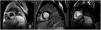

The cardiac magnetic resonance (CMR) revealed an infiltrative mass measuring 23mm in the mid and apical segments of the inferior wall. The characteristics of the mass, such as increased T2 signal (Fig. 1A) and delayed enhancement sequences (Fig. 1B), heterogeneous enhancement on perfusion (Fig. 1C), were consistent with cardiac tumor, and possible metastasis. Pericardium showed no alterations. Additionally, the CMR also identified a paraesophageal lesion.